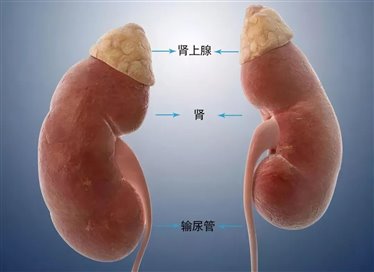

肾上腺是位于肾脏上方的两个小腺体,左右各一个,虽然体积只有拇指大小,却是人体重要的内分泌器官,能分泌多种激素,比如调节血压的醛固酮、应对压力的皮质醇,以及少量性激素等,这些激素维持着身体的水盐平衡、新陈代谢和应激反应。堪称身体的“激素工厂”。

然而,当肾上腺出现异常增生,形成肾上腺腺瘤时,可能会给患者的健康带来一系列潜在的风险和挑战。